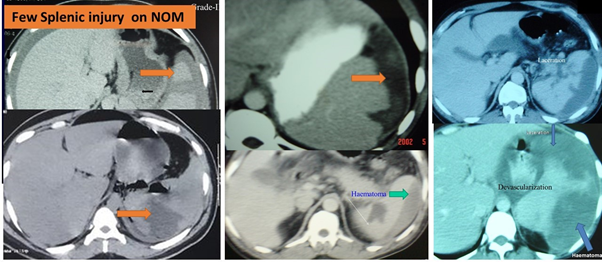

There were 72 patients with 73 abdominal organs injury (one patients had two organs, liver and right renal injuries). Modes of injury is given on Table 1. Age ranges from 8- 72 years (mean 30.70 SD13.759). There were 67 (93.54%) males and 5 (6.45%) females. Twenty (27.7%) patients received operative management and 41 (55.5%), non-operative management and eleven patients had twelve missed injuries (Table 2). Few CT images of splenic and liver injuries (Figure 1 & 2 respectively) are shown were managed by non-operative method. The details of organ wise injuries and their management is given (Table 2). The associated extra-abdominal injuries are shown (Table 3). Twelve organs injury were missed in eleven patients are given (Table2). Two liver injury patients received super selective angioembolization for haemostasis with the help of interventional radiologist. Six patients under went diagnostic laparoscopy (Two pancreas, four mesenteric injury). Amongst them, only one pancreatic injury patient a laparotomy was avoided (Figure 3) by putting a drainage tube and a feeding jejunostomy (FJ), where drained pancreatic juice was feed by the FJ. Second Pancreatic injury underwent ERCP and long pancreatic stenting with antibiotics and these two patients received high dose Omeprazole to reduce the pancreatic juice output. Two underwent left sided pancreatico-splenectomy for grade III pancreatic injury and other pancreatic injuries (grade-I and II) were managed conservatively with addition of high dose Omeprazole. The mean hospitalization period after reaching us, excluding the fatal cases were 9 +/- 2.74 days for (Non missed) and 10.5 +/- 1.93) days in missed group. There were three fatalities (Table 2). There were three (4.16%) morbidity in the form of superficial wound sepsis/ skin dehiscence.

Figure 1 (Few CT images with splenic injury).